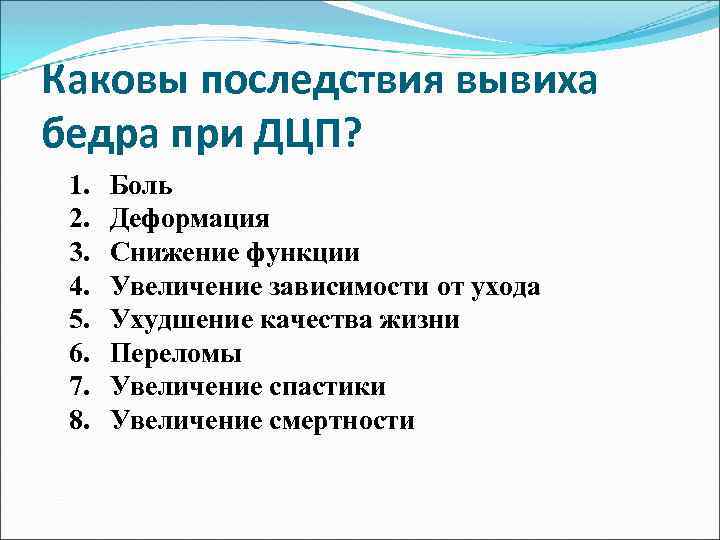

Каковы последствия вывиха бедра при ДЦП? 1. 2. 3. 4. 5. 6. 7. 8. Боль Деформация Снижение функции Увеличение зависимости от ухода Ухудшение качества жизни Переломы Увеличение спастики Увеличение смертности